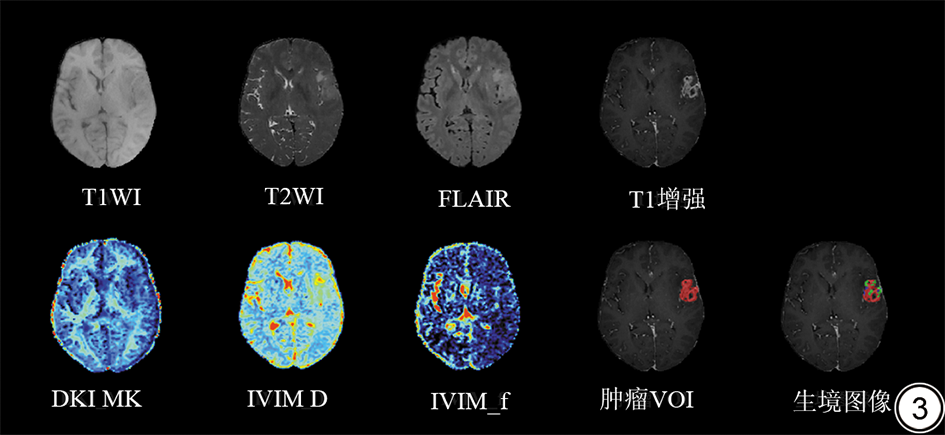

为提高数据聚类分析的效率,本研究采用了K-means算法构建生境图像,该算法作为目前最常用的聚类方法之一,具有计算简便和收敛速度快等优点[28]。在K-means算法中,输入了所有患者脑肿瘤VOI内每个体素对应的F、D和MK的成组数据,详细数据见表1。聚类数目通过轮廓系数(silhouette coefficient)确定(范围为2~6),当聚类数目为3时,轮廓系数最大曲率点出现(图1)。因此,本研究将脑肿瘤VOI划分成3个生境亚区(图2),分别为:生境1(高细胞密度低灌注高异质性生境);生境2(低细胞密度低灌注低异质性生境),生境3(高灌注低异质性生境)。其中,生境1中IVIM_D、IVIM_f和DKI_MK的范围分别见表1。结构MRI、DWI模型参数图及对应ROI勾画和生境图像见图3,随后分别计算每个生境亚区的体积占总体VOI体积的比值。

图3  一例62岁男性IDH野生型胶质母细胞瘤患者的结构MRI、DKI与IVIM参数图及对应VOI勾画与生境图像。生境图像中红色为生境1区域,绿色为生境2区域,蓝色为生境3区域。IDH:异柠檬酸脱氢酶;IVIM:体素内不相干运动模型;D:真实扩散系数;f:灌注分数;DKI:扩散峰度成像;MK:平均扩散峰度;VOI:感兴趣容积。

Fig. 3  Structural MRI, DKI and IVIM parameter maps, VOI delineation, and habitat imaging in a 62-year-old male patient with IDH–wild-type glioblastoma. IDH: isocitrate dehydrogenase; IVIM: intravoxel incoherent motion model; D: true diffusion coefficient; f: perfusion fraction; DKI: diffusion kurtosis imaging; MK: mean kurtosis; VOI: volume of interest.